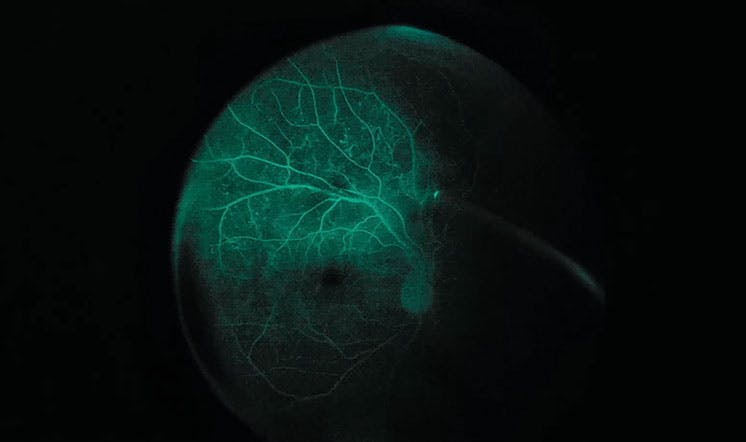

<p>Figure 2. The patient depicted here is undergoing vitrectomy for the treatment of PDR. This image illustrates the typical IOFA view the surgeon has while delaminating the vascular epiretinal membranes using a bimanual technique.</p>

Figure 2. The patient depicted here is undergoing vitrectomy for the treatment of PDR. This image illustrates the typical IOFA view the surgeon has while delaminating the vascular epiretinal membranes using a bimanual technique.

IOFA provides additional helpful information to guide and enhance many surgical decisions.9 A delay in vascular filling time can be observed if blood pressure is low, IOP is high, or a combination of both.21 Vascular epiretinal membranes are well visualized, and the contrast between the vascularized fluorescent vessels and a dark background is helpful to visualize the correct surgical plane to delaminate (Figure 2).22 Once delamination is complete, both areas of residual abnormal vascularities and retinal ischemia can be visualized.